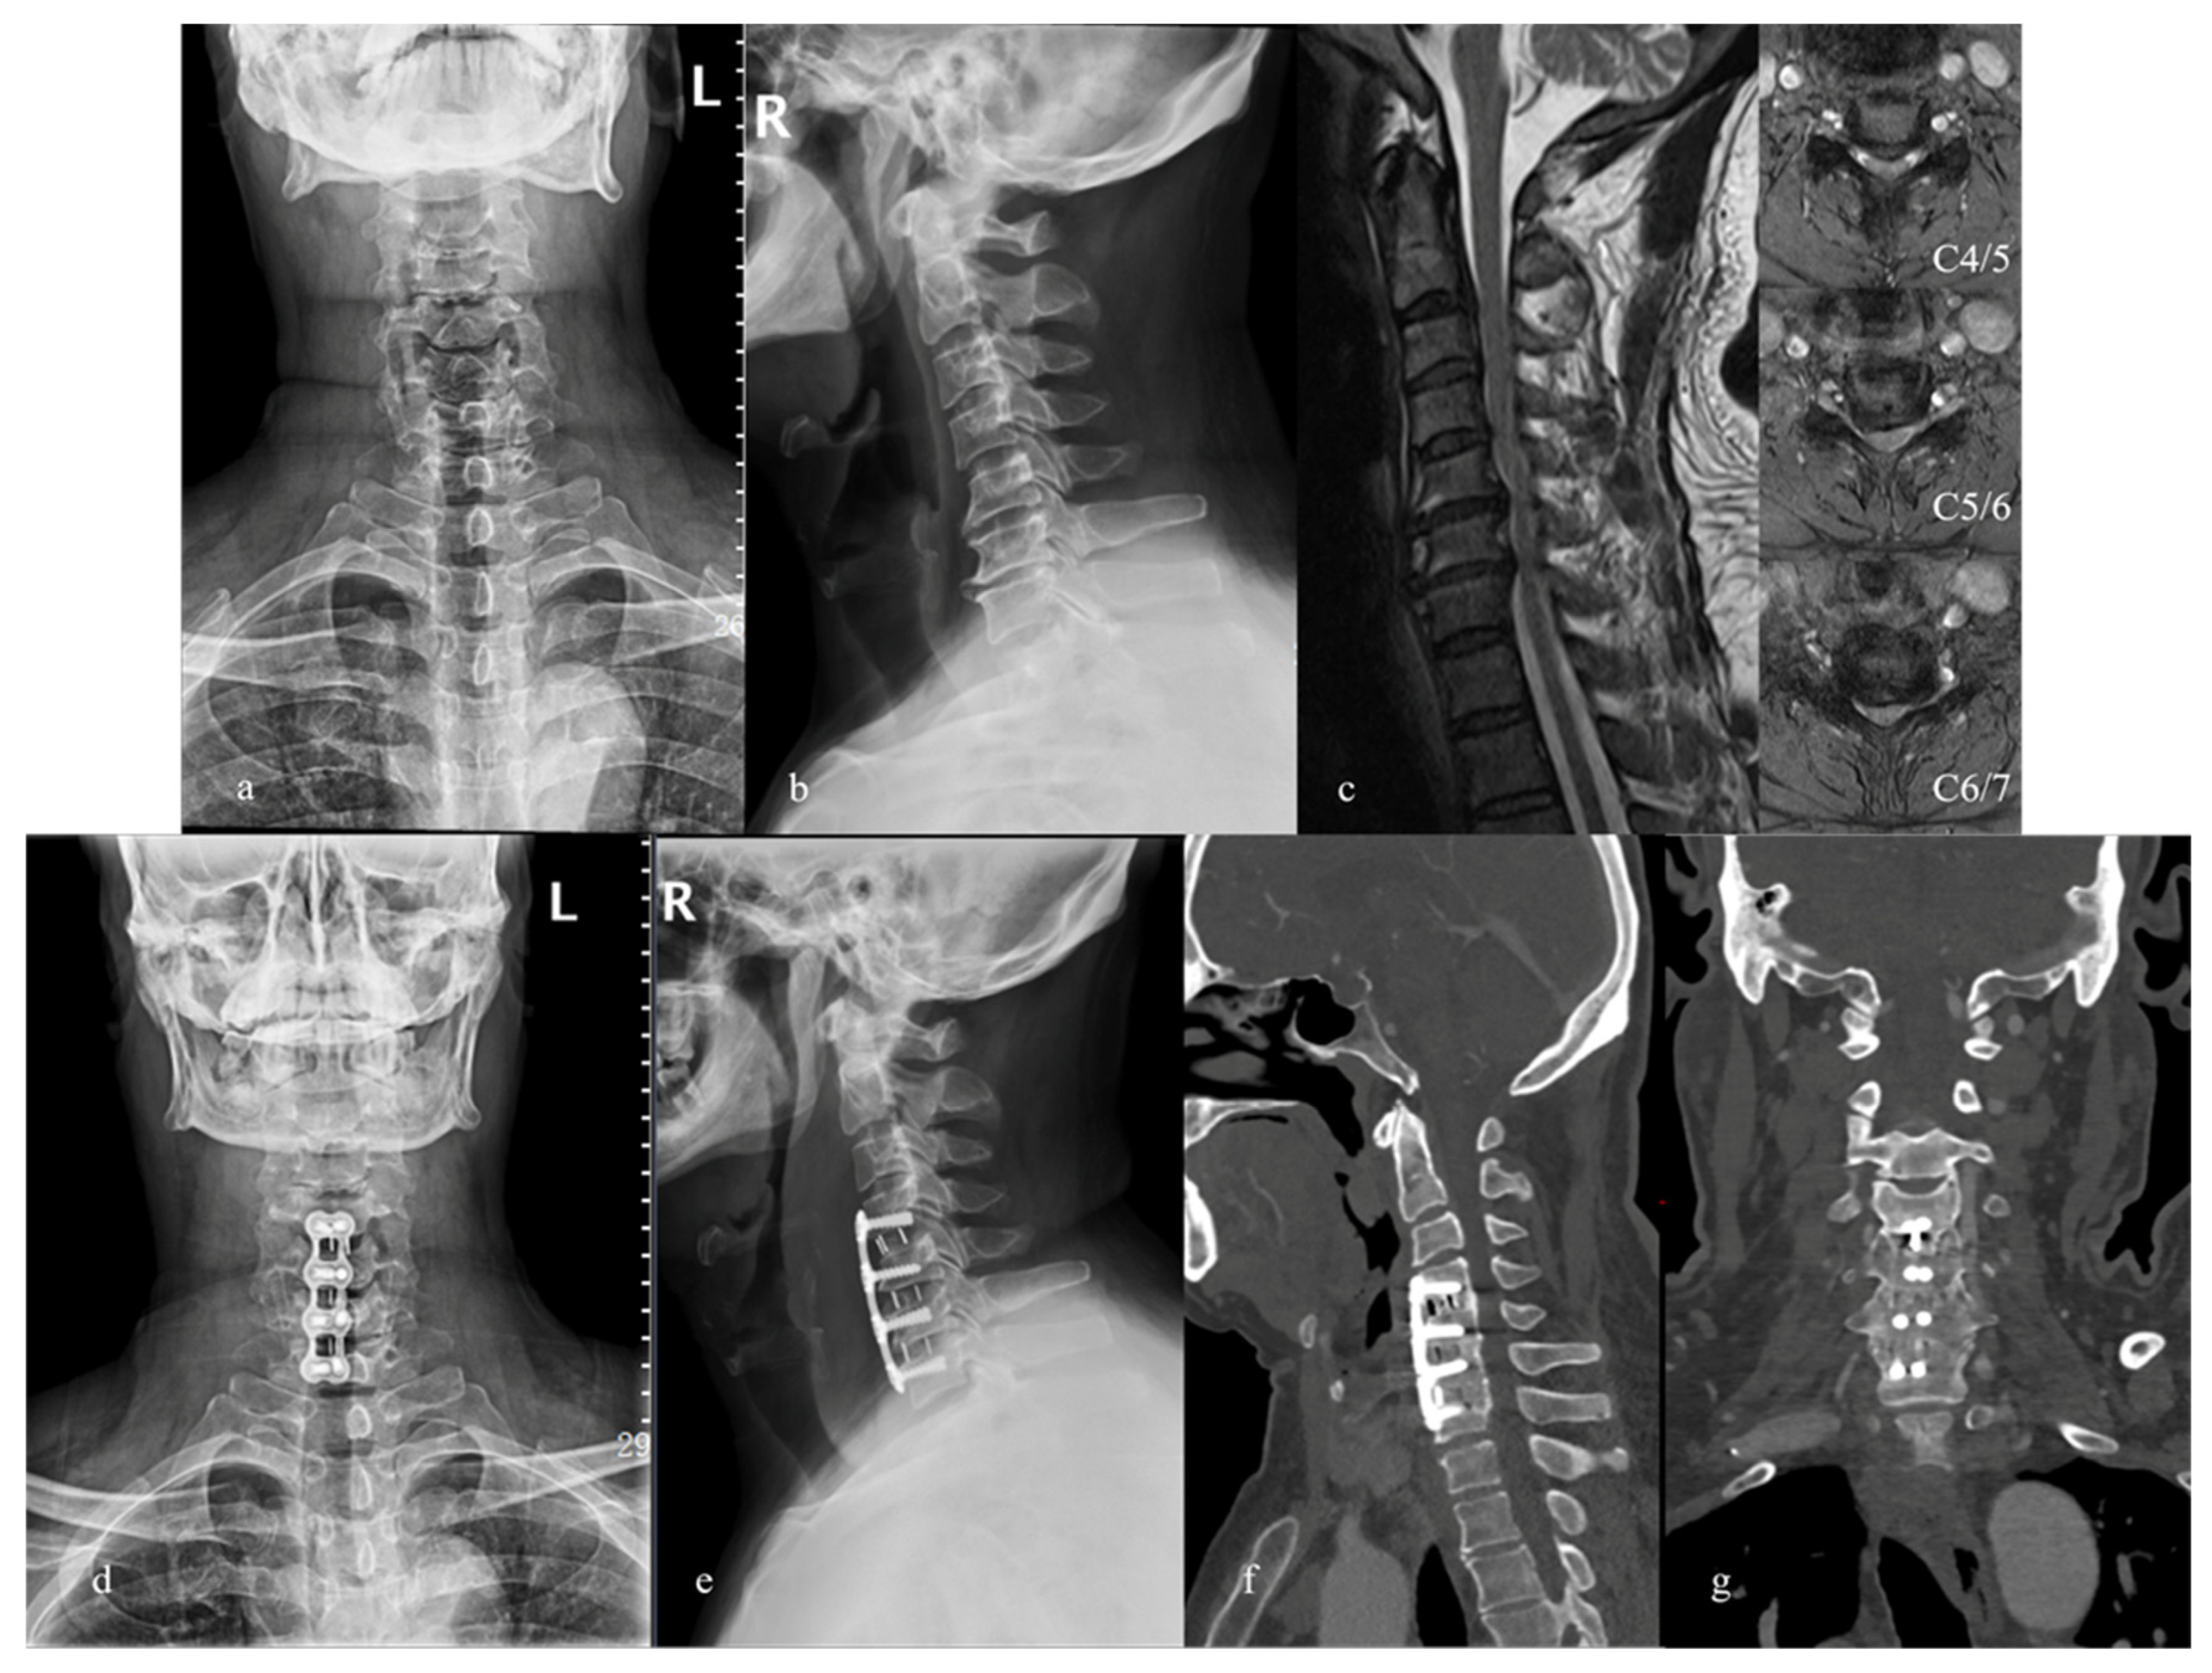

- Chen, Y.; Liu, Y.; Chen, H.; Cao, P.; Yuan, W. Comparison of Curvature Between the Zero-P Spacer and Traditional Cage and Plate After 3-Level Anterior Cervical Discectomy and Fusion: Mid-term Results. Clin. Spine Surg. 2017, 30, E1111–E1116. [Google Scholar] [CrossRef]

- Sun, B.; Shi, C.; Wu, H.; Xu, Z.; Lin, W.; Shen, X.; Wu, X.D.; Zhang, Y.; Yuan, W. Application of Zero-profile Spacer in the Treatment of Three-level Cervical Spondylotic Myelopathy: 5-year Follow-up Results. Spine 2020, 45, 504–511. [Google Scholar] [CrossRef]

- Xiao, B.; Wu, B.; Rong, T.; Cui, W.; Sang, D.; Liu, B. Clinical impact of 3-level anterior cervical decompression and fusion (ACDF) on the occipito-atlantoaxial complex: A retrospective study of patients who received a zero-profile anchored spacer versus cage-plate construct. Eur. Spine J. 2021, 30, 3656–3665. [Google Scholar] [CrossRef]